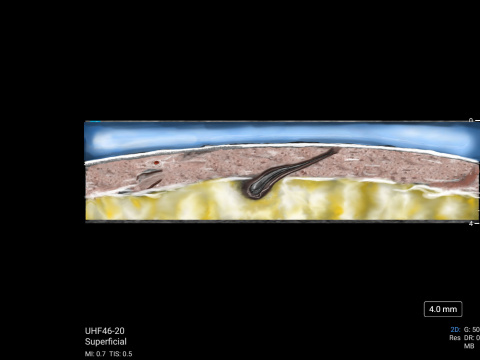

MSK Market Development Director, Daniel Shelton, shows off the capability of Sonosite UHF 46-20 with scans of a hair follicle and a vein. The scans were then illustrated to reveal details less obvious to the non-clinical eye.

Hair follicle on the back of a child's calf